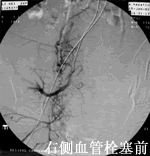

子宫动脉栓塞术后仍有可能妊娠